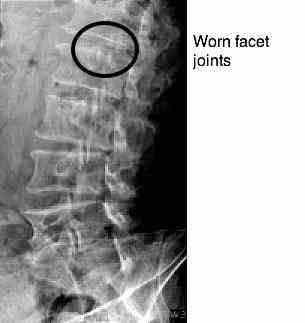

As expected, he has marked loss of disc space at L3-L4, and the oblique reveals degenerate facets at two levels: L1-L2 (hence the groin pain) and L3-L4 (anterior thigh pain).

Mr R almost certainly has fairly severe loss of the foraminal space, from a previous injury causing loss of the disc space. The front (inferior) facet then becomes degenerate, often forming a sharp scimitar that threatens the nerve root. It's not impossible that there is a capsular cyst, seen only on MRI, threatening the nerve root. I really should have ordered at least an X-ray and probably an MRI.

Only 10 percent of lower back surgery involves the femoral n. which emerges higher in the lumbar spine than the sciatic n. and it often involves degenerate facet joints, rather than disc prolapse. However, yours truly has just suffered a sequestered disc causing severe femoral nerve damage and upper leg pain, especially the front of the leg; but it is less common that back of the thigh, calf and foot pain, sciatic nerve.